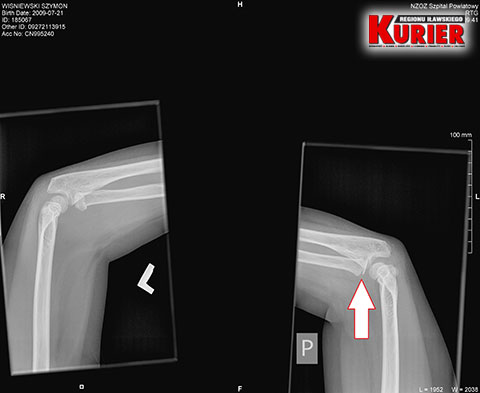

– Tu pan doktor, w odróżnieniu do lekarki w Iławie, zlecił wykonanie prześwietlenia jednej i drugiej ręki, dla porównania – opowiadała nam pani Karolina. – Gdy tylko zobaczył zdjęcie, od razu stwierdził złamanie łokcia z przemieszczeniem. Nie było już pytania, czy dziecko chce mieć założoną szynę czy nie. Od razu to zrobiono i skierowano nas do Olsztyna.

– Pytałam tam doktora, czy na zdjęciu z prześwietlenia w Iławie widać złamanie – mówiła w rozmowie z nami kobieta. – Oczywiście potwierdził i pokazał mi nawet, gdzie dokładnie do niego doszło. Konieczna była prawie godzinna operacja, podczas której ustabilizowano rękę drutem. Przeprowadzono ją od razu, bo lekarz mówił, że każda minuta w tym stanie jest na niekorzyść dziecka.

W iławskim szpitalu dziecku wykonano prześwietlenie

jednej ręki i dopatrzono się jedynie stłuczenia

W nowomiejskim szpitalu dla porównania

wykonano prześwietlenie obu rąk i stwierdzono

w lewej złamanie łokcia z przemieszczeniem